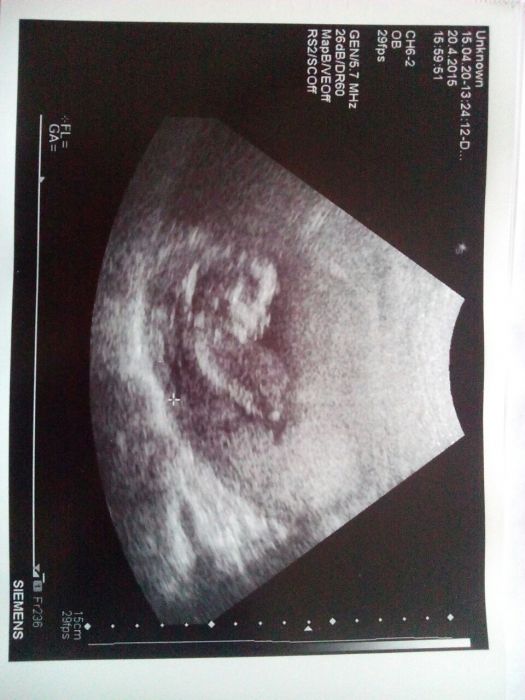

Ahoj holky...tak jsme po kontrole a uzasny zazitek. Miminko jsme vzbudily...tak bylo na 3D snimcich videt jak zyva a protahuje se :-) . Uz mame 13cm a krasne rosteme. Dokonce mi doktorka dala kratke video ve 3D

Ahoj děvčátka :) tak dneškem pro me skoncila nejistota :-)... 1.screening negativni..riziko 1:3.600..mimco krasne poskakovalo a dle ultrazvuku jsme zas vetsi...misto 14+2 jsme 14+5 ale doktor uz to neresi...pocitame to od minule jako 14+2 :)... Jinak mame po zadecek 8,5 cm...stehenni kost mela 1,5 cm...takze doktor rikal ze rosteme ukazkove a celkove mame asi 10,5-11 cm... :-D.... Dalsi ultrazvuk v 16tt takze hned 4.5 :)....